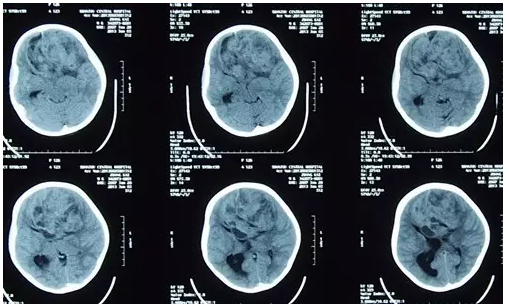

患儿张某某,男,6岁,无明显诱因出现恶心、呕吐症状持续1月余,未在意,遂渐出现头痛增加,呕吐症状明显,外院就诊,CT显示双侧额叶区巨大占位,家属为求有效治疗,来我院就诊。

图1:外院CT显示双侧额叶区巨大占位

入院后完善检查,术前CT显示可见多发斑片状低密度影,病变范围9.7CM×7.33CM,鉴于患儿病情危重,科室在急诊全麻下行双侧额叶巨大占位性病变切除术,手术由神经外一科主任张良主刀完成,术程顺利,术后诊断:双侧额叶巨大肿瘤。术后病理:间变型脑室外神经细胞瘤 WHOⅢ级。